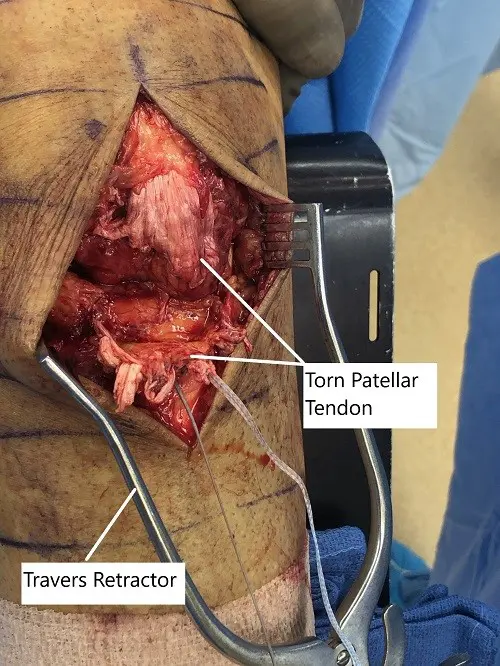

The incision was planned from the anterior part of the patellar to the tibial tuberosity. A midline incision was given. With sharp and blunt dissection, a patellar tendon was reached, which was found to be ruptured with ragged margins.

The tear was extending into the lateral and medial patellar tendon. The knee was opened and washed thoroughly with irrigation. The ragged margins of the patellar tendon were removed. The primary repair of the patellar tendon was planned.

Intraoperative image showing the torn patellar tendon